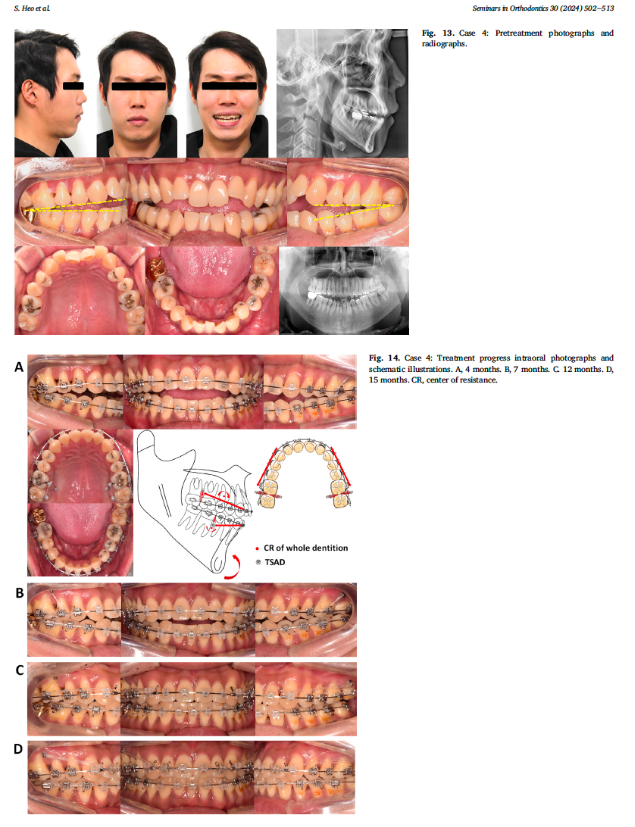

Bệnh nhân nam 31 tuổi đến khám với lý do chính là cắn hở trước (AOB) và nụ cười kém thẩm mỹ. Khám lâm sàng cho thấy bệnh nhân có kiểu xương loại II tăng chiều cao (skeletal Class II hyperdivergent pattern) , môi không khép kín (lip incompetency), lộ răng cửa hàm trên không đủ, và đường cong nụ cười ngược (reverse smile arc) khi cười, mặt phẳng cắn dạng chữ V (V-form OP) không có tiếp xúc ở răng hàm nhỏ (Hình 13).

Điều trị được thực hiện bằng làm lún toàn bộ cung răng và kéo lùi (total arch intrusion and retraction) ở cả hai hàm, sử dụng TSADs đặt ở phía má và khẩu cái (buccal and palatal TSADs) (Hình 14).

Kết quả đạt được bao gồm: sự hài hòa đường nét khuôn mặt, điều chỉnh AOB thành công, và cải thiện nụ cười thẩm mỹ nhờ thay đổi mặt phẳng cắn (OP change) và tự xoay hàm dưới ngược chiều kim đồng hồ (CCW rotation) .

Tổng thời gian điều trị là 26 tháng. Phác đồ duy trì giống như các ca trước, gồm cố định duy trì ở răng trước, hàm duy trì tháo lắp wraparound, lưới chặn lưỡi, và hướng dẫn tư thế lưỡi. Sau 1 năm duy trì, kết quả điều trị vẫn được bảo tồn, không có tái phát AOB (Hình 15).